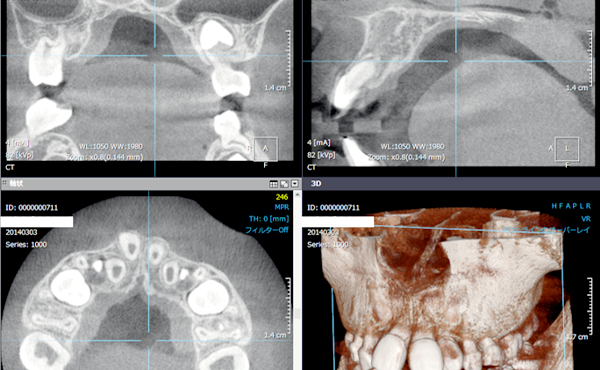

CT

通常のレントゲンでは、判らない病状を、詳しく確認できます。より的確な診断が可能に。撮影は保険適応です。